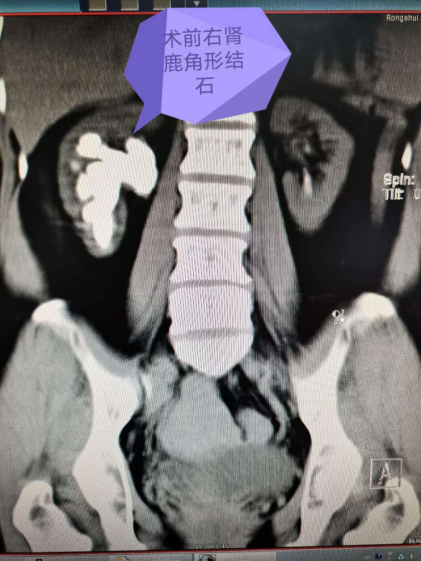

三、泌尿外科疾病:开展腹腔镜下肾上腺疾病治疗、腹腔镜下肾切除术、腹腔镜下输尿管切开取石术、腹腔镜下膀胱修补术等微创手术。提供经皮肾盂镜碎石取石术(PCNL)、经输尿管镜碎石取石术、经输尿管软镜碎石取石术、经尿道膀胱经碎石取石术等一站式泌尿系结石治疗方案。开展前列腺电切术及前列腺介入栓塞术。常规开展肾脏、膀胱、前列腺恶性肿瘤的切除手术及介入治疗。同时在积极探索泌尿男科的前沿发展。

经输尿管软镜联合经皮肾镜手术  |